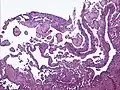

Micrograph of a kaposiform hemangioendothelioma with "glomeruloid" nodules of endothelial cells.

• Kaposiform hemangioendothelioma (also known as "Infantile kaposiform hemangioendothelioma"[3]) is an uncommon vascular tumor, first described by Niedt, Greco, et al. (Hemangioma with Kaposi's sarcoma-like features: report of two cases.(Niedt GW, Greco MA, Wieczorek R, Blanc WA, Knowles DM 2nd. that affects infants and young children, with rare cases having also been reported in adults. Pediatr Pathol. 1989;9(5):567-75.)[2]: 596 [3]: 1782